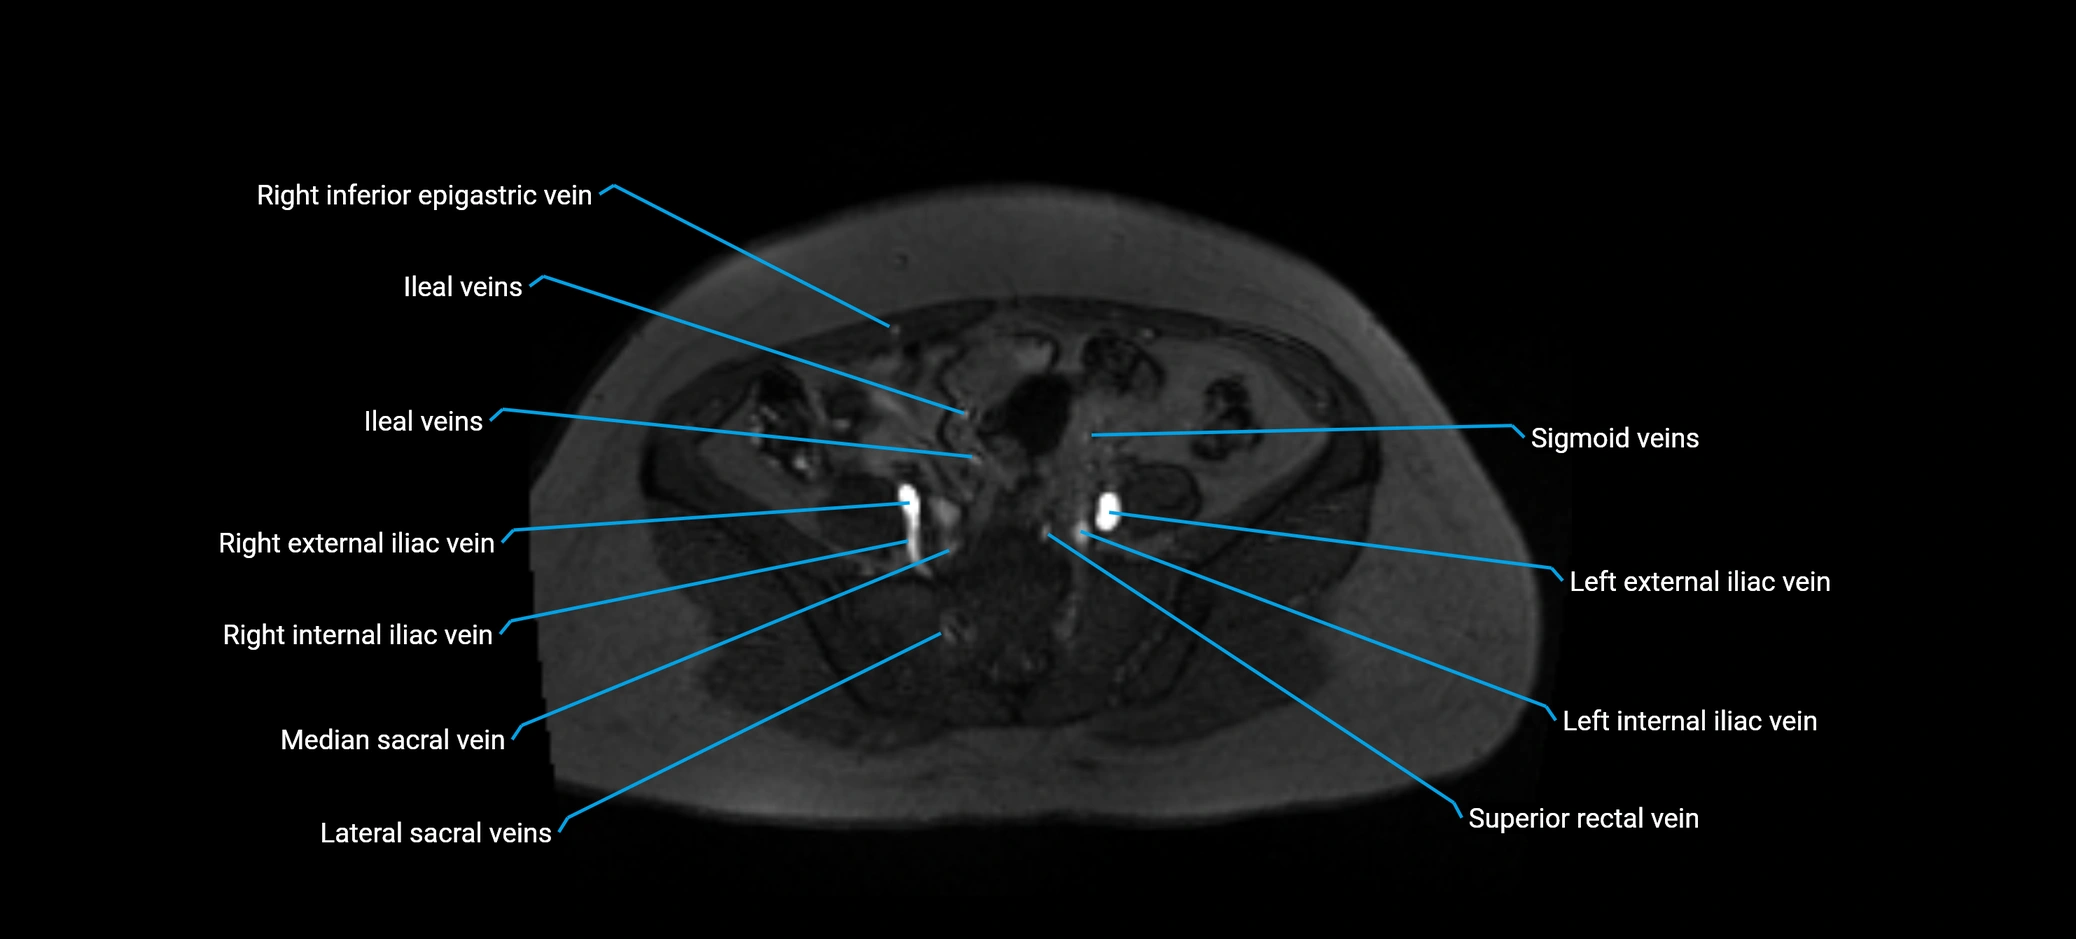

MRI image

image